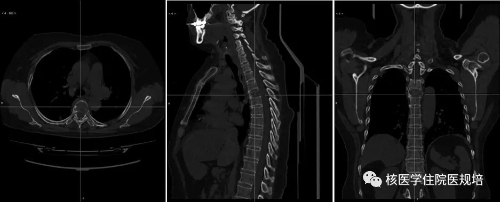

病史及检查目的: 患者63岁女性,4月余前无明显诱因出现持续性胸背部疼痛,沿肋间放射至胸部,左侧重,翻身及行走后加重,查体T4棘突压痛及叩痛(+)。行胸椎CT平扫+三维重建提示T4椎体变扁,后缘可见软组织密度影突向髓腔内,硬膜囊受压,考虑T4椎体病理性骨折可能。实验室检查:尿本周蛋白阴性;尿KAPPA轻链及LAMBDA轻链阴性;肿瘤标志物检测均为阴性。 为明确T4椎体病变性质、寻找骨转移原发灶行PET/CT检查(图2)。 图1.胸椎CT(骨窗) 图2. PET/CT图像 检查所见: T4椎体及附件区域见条状高度放射性浓聚(SUVmax:8.1),CT于相应区域可见溶骨性骨质破坏及软组织肿物影,向后累及附件并突入椎管内,椎体前缘骨皮质尚完整。左腋窝可见一FDG摄取增高淋巴结显影,考虑淋巴组织回流所致。扫描范围其余部位未见明显异常。 检查意见: T4椎体及附件骨质破坏呈葡萄糖代谢明显增高考虑恶性肿瘤可能,需鉴别原发灶不明的转移瘤、浆细胞瘤、骨巨细胞瘤、骨的嗜酸性肉芽肿及不典型淋巴瘤等,建议组织病理学检查。 手术及病理: 行胸椎椎管减压、椎弓根钉内固定术、病灶清除、椎体成形术,积水潭医院病理会诊:(胸4椎体)富含多核巨细胞病变,组织形态首先考虑骨巨细胞瘤。免疫组化:CK(-),Desmin(-),Ki67(10%-15%+),Vimentin(+),ActinSM(-),PGM-1(多核巨细胞+),KP-1(多核巨细胞+)。 病例相关知识: 骨巨细胞瘤(giant cell tumor of bone,GCT)为一种临床较为常见的骨原发性肿瘤,大部分为良性肿瘤,部分生长活跃,极少数一开始就是恶性。GCT具有丰富的血管组织并含有单核基质细胞和很多破骨细胞样的多核巨细胞,其中基质细胞决定肿瘤的性质。Jaffe等[1]首次定义GCT并根据基质细胞的异型性及有丝分裂活动进行病理分级,一般认为I级偏良性,Ⅲ级为恶性,介于两者之间的为Ⅱ级。目前WHO第四版骨与软组织肿瘤已将GCT定义为交界性肿瘤。与西方国家相比,国内GCT的发病率较高,约占所有原发骨肿瘤的20%[2]。女性发病率高于男性,多发生于青壮年,发病年龄多在20-40 岁之间,50岁以上的GCT约占9%-13%,青年人和儿童少见[3]。GCT多发生于骨骺融合后成熟的骨端[4],侵犯长骨多见,*常见于股骨下端、胫骨上端,约占50%以上,发生于非长管状骨如脊柱、骨盆、手骨、颌骨、颅骨等的GCT约占20%,但近年来也有报道GCT在脊柱的发病率增加。该病*常见的症状为肿瘤部位的疼痛与肿胀,且疼痛有活动后加重、休息后缓解的特点,手术是治疗GCT的主要方法,目前亦有一些RankL拮抗剂用于术前药物治疗。 GCT的影像表现具有一定特异性,X线平片表现为骨端偏心性、囊性、膨胀性、溶骨性骨质破坏, 无明显硬化缘,骨包壳完整或部分缺如,部分肿瘤内可见骨性分隔,呈“皂泡样”改变(图3)。CT较X线具有较高的分辨率,能更加细致入微地观察骨质破坏情况,可观察到骨质破坏区内残留的骨嵴,与X线平片上“皂泡样”改变相对应,还可以能清晰地显示破坏区内部结构及软组织肿块及周边残留的骨壳。MRI检查能够清晰显示骨巨细胞瘤的大小、位置及形态,且对肿瘤附近的水肿状况进行清晰显示,在诊断病变范围上的价值较X线与CT检查更高。在MRI检查中,肿瘤的实质部分多呈T1WI与T2WI等信号,其内常可见多发混杂信号影,提示肿瘤内部常伴有坏死、囊变和出血。 图3. 骨巨细胞瘤的皂泡样改变(左:X线片,右:99mTc-MDP骨显像)(北京大学人民医院提供) 尽管骨肿瘤的*终诊断的确立需要临床、影像、病理三结合,即“CRP诊断”,但典型的影像表现对早期临床诊疗决策的建立十分重要。18F-FDG PET/CT全身大视野成像有助于发现肿瘤累及区域,通过发现多发病灶,首先可帮助检出转移瘤或血液系统肿瘤。然而,本病例PET/CT所见为脊柱单发病变,其鉴别诊断面临更多的挑战。由于病灶呈溶骨性骨质破坏并软组织肿物形成,椎体出现病理性骨折且软组织肿物压迫硬膜囊,同时肿瘤呈FDG高摄取,鉴于患者年龄偏大,应首先怀疑恶性病变。患者无肿瘤标志物升高且PET/CT无原发肿瘤病灶显示,不支持上皮源性肿瘤脊柱转移,但从发病机率应考虑有无原发灶隐匿的可能性;病变椎体前缘保留较完整,提示肿瘤侵袭性不强,不符合侵袭性淋巴瘤或一些高度恶性肉瘤的常见表现;单发浆细胞瘤多为溶骨性且可呈膨胀性改变,破坏区可见残留的骨壳和骨嵴,但一般FDG摄取程度相对较低;骨的嗜酸性肉芽肿属于朗格汉斯组织细胞增生症虽可累及脊柱并出现病理性骨折,其FDG摄取程度亦较高,但该病多见于年轻人群。回顾性分析该患者年龄虽然不属GCT好发人群,但亦可发病,而较高的FDG摄取和较温和的骨质破坏可符合GCT表现,然而由于椎体压缩性骨折使得CT对肿瘤形态和内部结构改变的观察不满意。若能获得典型的GCT CT表现,GCT诊断应该首先考虑(图4)。 图4.典型脊柱骨巨细胞瘤的PET/CT及MRI(北京大学人民医院提供) 对于原发性骨肿瘤,18F-FDG PET/CT的摄取与肿瘤成分密切相关,富含巨细胞的肿瘤(骨巨细胞瘤、未分化肉瘤、朗格汉斯组织细胞增生症等)多可见较高FDG摄取,甚至高于常见的恶性骨原发性肿瘤(骨肉瘤、软骨肉瘤、尤文肉瘤等),而良性肿瘤或者细胞成分稀疏的恶性肿瘤FDG摄取程度较低。 小结: 本病例并非典型的骨巨细胞瘤,通过此病例提出这一临床可能遇到的情况,希望为规培的小伙伴们提供脊柱病变的鉴别诊断思路。同时强调对于骨肿瘤的诊断一定是临床、影像、病理的综合分析,对常见的骨原发肿瘤相关知识应加以了解。 作者:中日友好医院核医学科 韩萍萍 郑玉民 参考文献: [1] Jaffe Hk, Lichtenstein L, Portis RB. Giant cell tumor of bone: Its pathologic appearance, grading, supposed variants and treatment. Arch Pathol, 1940, 30: 993. [2] Szendröi M. Giant-cell tumour of bone. J Bone Joint Surg Br, 2004, 86: 5-12. [3]Murphey MD, Nomikos GC, Flemming DJ, et al. From the archives of AFIP. Imaging of giant cell tumor and giant cell reparative granuloma of bone: radiologic-pathologic correlation. Radiographics, 2001, 21: 1283-1309. [4] 段承祥,王晨光,李健丁主编. 骨肿瘤影像学. 科学出版社, 2004年第一版。